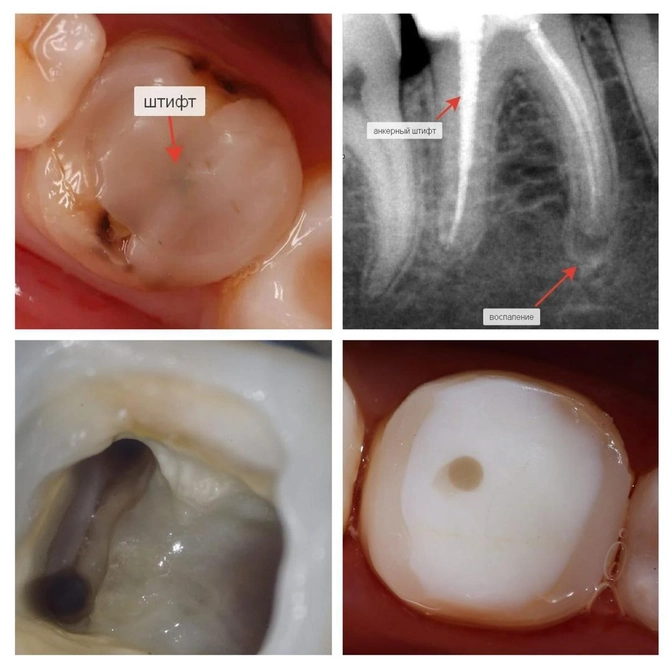

Требовалось перелечивание "шестерки" перед началом ортолечения.

• Зуб ранее пролечен резорцин-формалином.

Тот самый "розовый зуб" или Russian Red Tooth, о котором я писала не так давно.

Метод устаревший, не позволяет полностью заполнить пустоты в каналах и там разрастается воспаление.

А зуб тем временем краснеет-розовеет, становится хрупким, как стекло, а каналы плотно зарастают.

• Пломба была большая, практически на всю жевательную поверхность.

• Стенка зуба от нагрузки откололась — это ворота для попадания инфекции внутрь.

• На верхушках корней воспаление.

• Плюс ко всему зуб был укреплен анкерным штифтом.

✔️Очистила полость и каналы от старой пломбы;

✔️Убрала анкерный штифт;

✔️Заложила лекарство для лечения воспаления;

✔️Восстановила стенку зуба и закрыла временной пломбой.

Каналы полностью очистили — аж сверкают чистотой!

Запломбировали и восстановили зуб композитом.

Через полтора года от воспаления не осталось и следа.